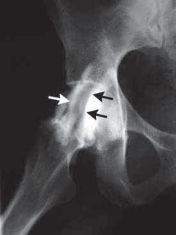

8. Iliopsoas bursography and ultrasonography may be helpful to rule in, but not rule out, the diagnosis (

FIG 3

).

FIG 3•

Iliopsoas bursography silhouettes the iliopsoas tendon (

arrows

) with contrast.

A.

In flexion, the iliopsoas tendon lies lateral to the femoral head.

B.

In extension, the iliopsoas tendon moves medial. (Courtesy

A B of J. W. Thomas Byrd, MD.)